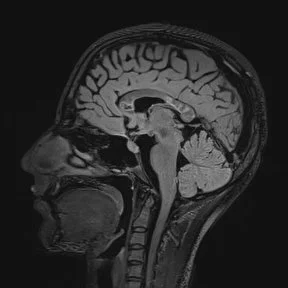

• Note: MS lesions typically involve the callososeptal interface (first picture) and extend up into the callosal substance.

• Callososeptal interface: inferior surface of the corpus callosum, where the septum pellucidum abuts it.